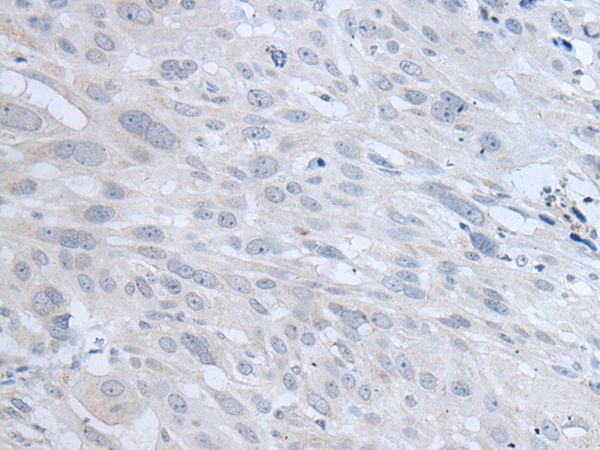

ELISA, IHC |

IHC positive control: |

Human esophagus cancer and human lung cancer |

IHC Recommend dilution: |

20-100 |